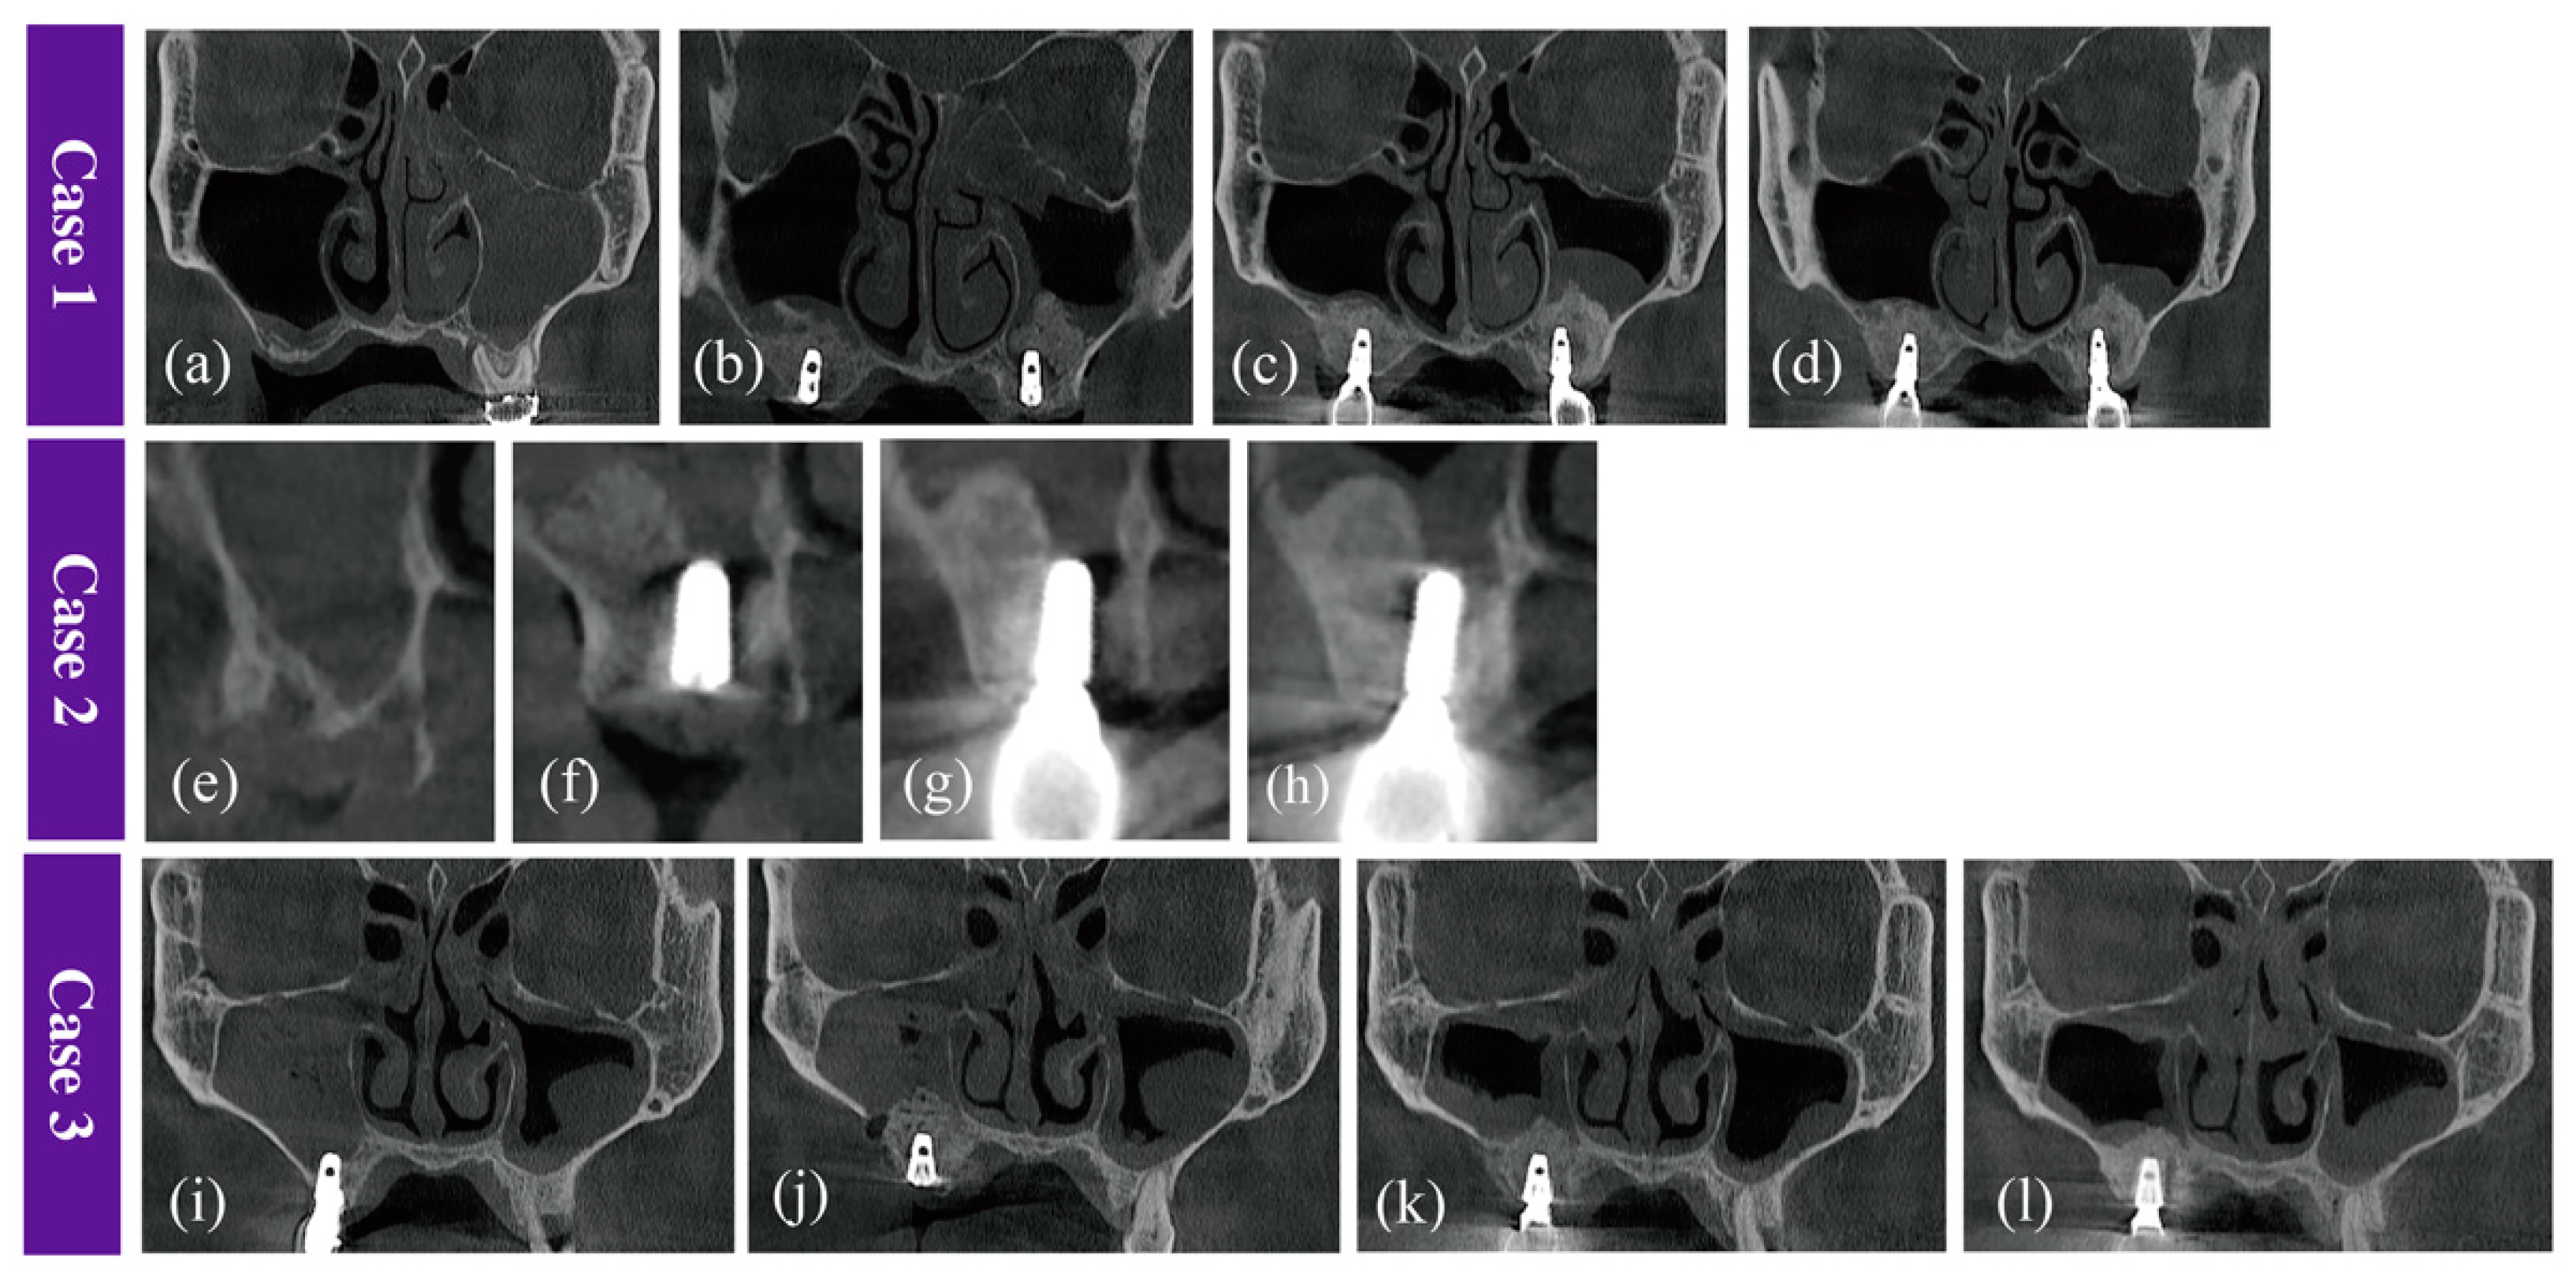

2.2.1. Case 1

2.2.2. Case 2

2.2.3. Case 3

2.5. Radiological Findings